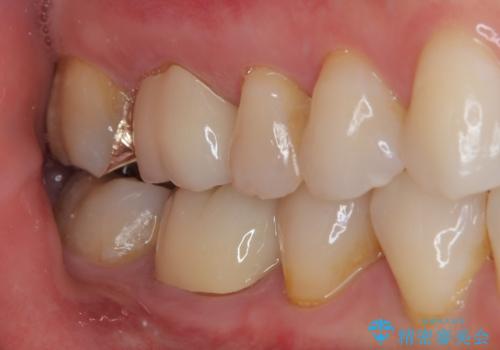

- 当院で矯正終了後に銀歯をやり替えたいとのことで来院された患者様です。

右上の6番目の歯はメタルインレーが大きかったためルジルコニアクラウン、右上の7番目の歯は一番奥で審美的な要素よりも機能面を重視してゴールドインレー修復による治療計画を立案しました。

拡大鏡視野下で保険のプラスチック(コンポジットレジン)、虫歯を除去し、フルジルコニアクラウン、ゴールドインレーに適した形にしました。

歯と歯茎の間に圧排糸と呼ばれる糸を入れてシリコーン印象を行いました。

見た目と機能面ともに満足していただきました。